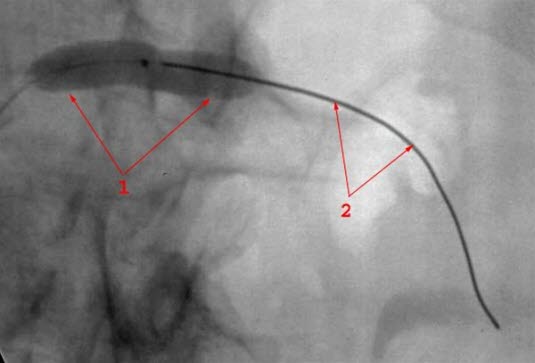

Dilatasjon av stenose i nyrearterien med 5 mm ballong

1. Ballong kateter

2. Mandreng